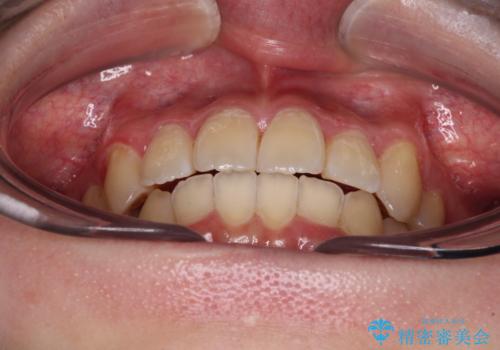

【モニター】八重歯と前歯のクロスバイト ワイヤーを併用しインビザラインで矯正治療

インビザラインでの治療を希望されていましたが、前歯のクロスバイトや下顎小臼歯の捻転が認められたため、インビザライン単独で治療を行うよりも、ワイヤー装置を併用した方が、治療期間の短縮やトラブル回避できると判断し、ワイヤー装置を併用することとしました。

まずはワイヤー装置により前歯のクロスバイトと下顎小臼歯の捻転を改善し、その後インビザラインにより全体を整える矯正治療を行うこととしました。